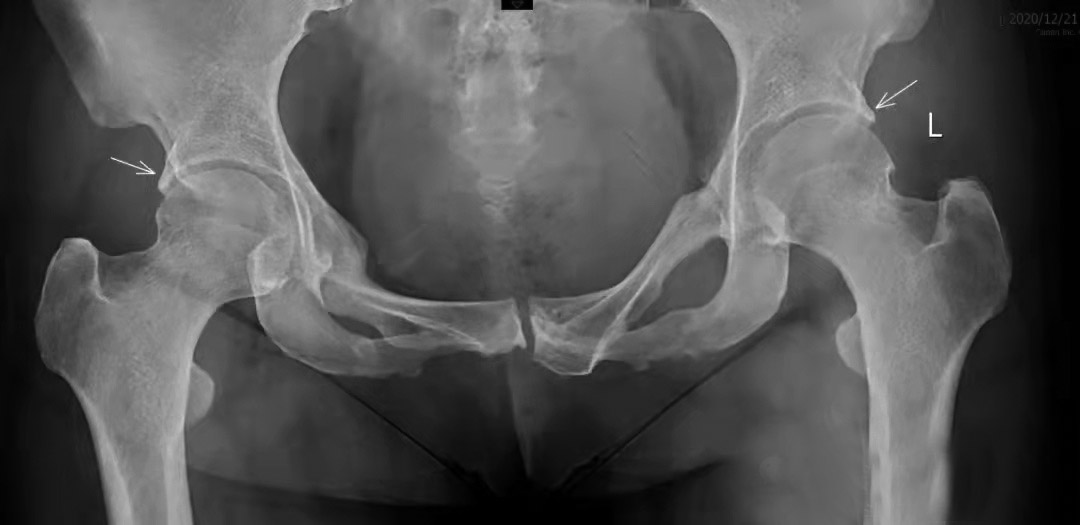

在治疗髋关节疼痛类疾病时,患者往往担心股骨头的血运问题。人体是一个大整体,髋关节是其中的一部分,股骨头和髋臼任何一方出了问题都会“报警”——疼痛或功能受限。 股骨头髋臼撞击综合征(FAI)是髋关节疼痛的常见原因之一,是股骨头颈部与髋臼边缘机械碰撞,导致相邻和对侧髋臼软骨发生损伤,被认为是导致髋关节骨性关节炎(OA)的主要原因。 FAI主要分为凸轮型和钳夹型,以及二者的混合型(约86%的患者为混合型)。 在凸轮型FAI中,股骨头颈交界处的骨性畸形在髋关节屈曲时进入髋关节,反复撞击髋臼盂唇,引起盂唇撕裂损伤,并造成髋臼周围软骨撕脱,即所谓的“地毯现象”。 在钳夹型FAI中,由髋臼内陷、髋臼后倾等导致的髋臼过度包容,使股骨头颈紧靠髋臼边缘,造成一个非常大的股骨头偏心距畸形,或引起股骨颈相对变宽、变短。一般来说,撞击部位位于髋臼前外侧,造成撞击部位盂唇硬化,但是局部损伤较小,对侧软骨损伤要比盂唇损伤的发生时间靠后。 FAI的发生和髋关节的形状密切相关,并且似乎具有高度遗传性,同时主要与生物力学存在密切关系。一般认为FAI和OA的发展之间的力学关系是这样的:凸轮型FAI继发OA被认为是由髋臼边缘盂唇和软骨,或者两者任何一方因撞击反复发生损伤造成的;而在钳夹型FAI中,股骨头前上部覆盖增加造成髋臼反复摩擦,从而发生损伤。回顾性研究和前瞻性研究均表明,FAI患者多并发OA,反之亦然。 症状轻微的患者口服非甾体抗炎药、休息即能改善;关节内注射玻璃酸钠或PRP(自体全血经离心后自体血小板的浓集物)能快速缓解疼痛,但彻底止痛、改善功能还要依靠外科手术。在这方面,开放性手术(就是传统的开刀手术,需要切开患者的皮肤以及皮下组织)和关节镜手术都能达到较好的疗效。从直观上讲,就是外科手术能够消除撞击,减少软组织结构的继发性损伤,避免髋关节进一步退变,从而阻止OA的发生。 下面介绍一个典型病例。 一名中年女性患者,无明确诱因出现双侧大腿内侧疼痛、下蹲受限。患者自述10年前有骨盆骨折病史,担心发生股骨头坏死,来到河南省洛阳正骨医院就诊。 我们看一下患者的X线片。 图1中箭头1和箭头2提示,双侧髋臼边缘包容过度,造成患者疼痛和活动受限。 放大之后看得更加清楚(图2)。 可以看到,患者的右侧股骨头外缘关节间隙狭窄,股骨头与髋臼的间隙不均匀,其“骨刺”其实就是不断损伤、钙化的盂唇。 综上所述,对患者进行特殊部位X线检查、CT检查、MRI(磁共振)检查,可进一步了解股骨头与髋臼的匹配关系、盂唇损伤钙化和股骨头骨髓水肿的情况,为下一步手术治疗提供依据。 (作者供职于河南省洛阳正骨医院)